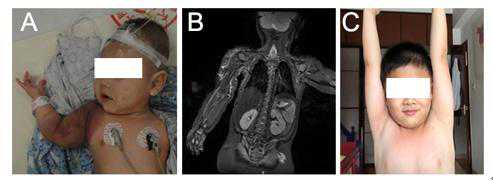

病例1:右面颈、胸壁广泛卡泼西样血管内皮瘤伴KMP,经过治疗后6年随访。

病例1:右肩部、上肢卡泼西样血管内皮瘤伴KMP,经过治疗后6年随访。

肩部巨大卡泼西样血管内皮瘤伴卡梅现象